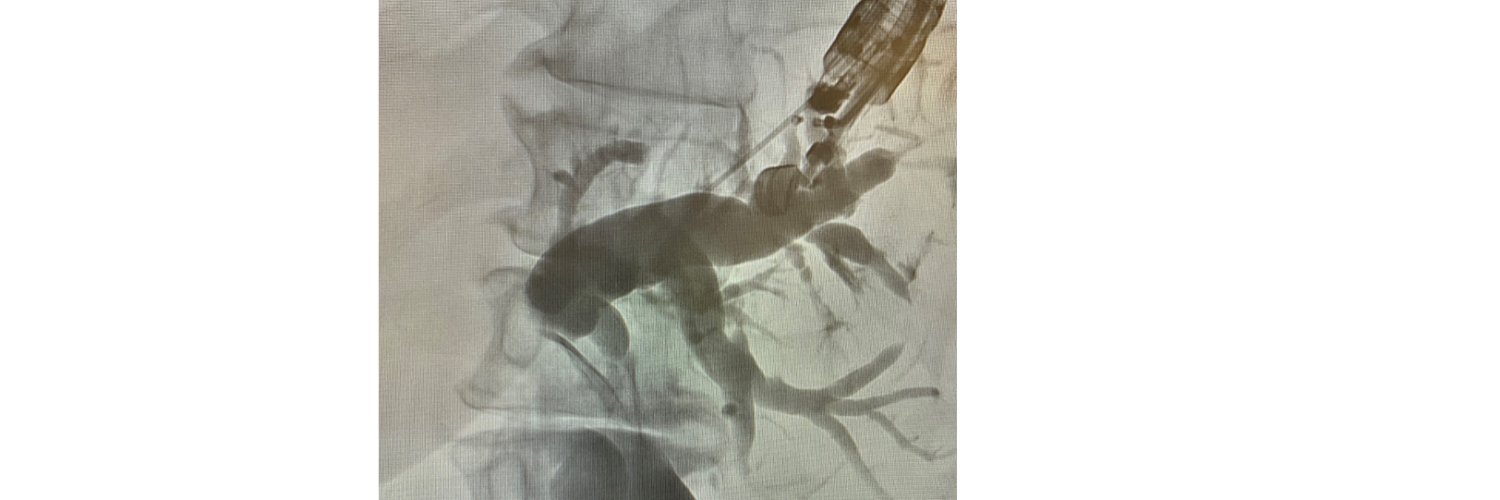

In this Review Article, Judy A. Trieu and Todd H. Baron coordinate "EUS-guided gastroenterostomy using direct needle-puncture technique." videogie.org/article/S2468-… @EndoTx @TrieuMD @KaraRaphael

1/2 ⁉️Novel application of PuraStat⁉️ Case: Minor defect after dual sphincterotomy with 5Fr x 2cm PD stent already in place Tx: PuraStat applied to create “sealant” & 5Fr x 7cm biliary stent placed to prevent obstruction. Both stents expected to spontaneously pass.